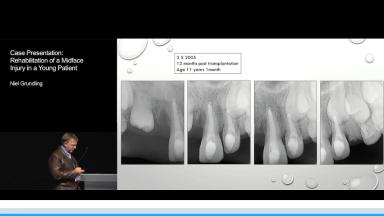

Case Presentation: Rehabilitation of a Midface Injury in a Young Patient

Niel Grundling

A 9 year old girl sustained severe soft tissue and facial bone injuries when a brick was thrown through the window of the vehicle in which she was travelling. The injuries included laceration and abrasion of the upper lip, nose and glabella, degloving of the midface, fracture of the frontal bone, nasal septum, nasal bones, nasal cartilage, dentoalveolar fracture and avulsion of teeth 12 and 11 and fracture of the incisal edges of the lower insicors.

The multidisciplinary approach to the management and rehabilitation of this young girl is presented which includes the initial, intermediate and final phases of treatment.